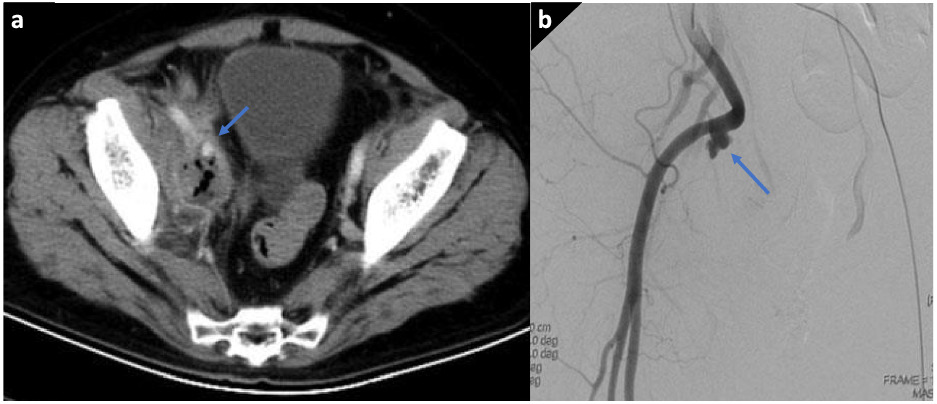

全腹增强CT(图1a)提示:右侧盆腔内混杂密度影,含有气体,右髂外动脉血管壁连续性差。

图1a、1b